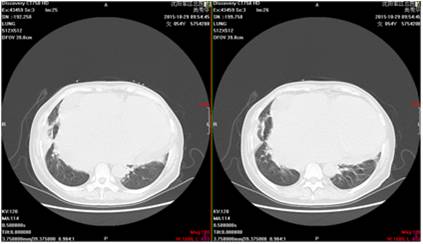

肺部CT示右肺下叶基底段见斑片状稍高密度,边界清晰。考虑:考虑右肺下叶炎症,不除外占位性病变。

(复查肺增强CT,炎症部分较前有所吸收,未发现肺部占位性病变)